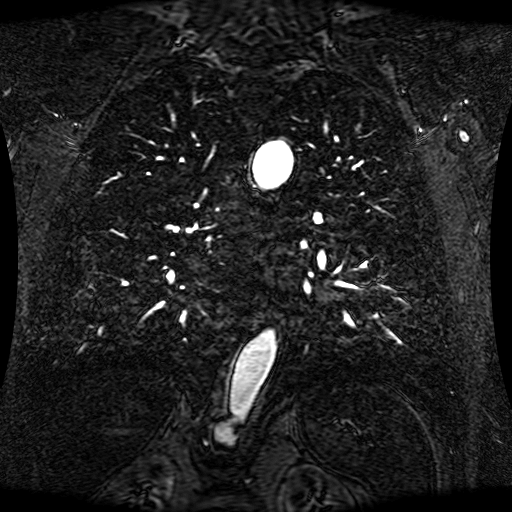

These magnetic resonance angiography (MRA) images show coronal slices acquired from consecutive anteroposterior positions within the torso. The study was performed on a 1.5T General Electric (GE) Signa imaging system with gadolinium-contrast-enhancement for visualization of the cardiopulmonary vasculature. The pulse sequence used was a 3D time-of-flight fast spoiled gradient recalled acquisition in steady state (FSPGR, TR=6.3, TE=1.4, NEX=1, FOV = 40cm, slice thickness = 1.2mm).

This sample image contains 76 frames. It is available in DICOM format (E1154S7I.dcm), as an animated GIF (E1154S7I.gif), as .ogg, .mp4, .webm, and .swf animations (one of which is shown above), or as individual PNG-format frames (see below).